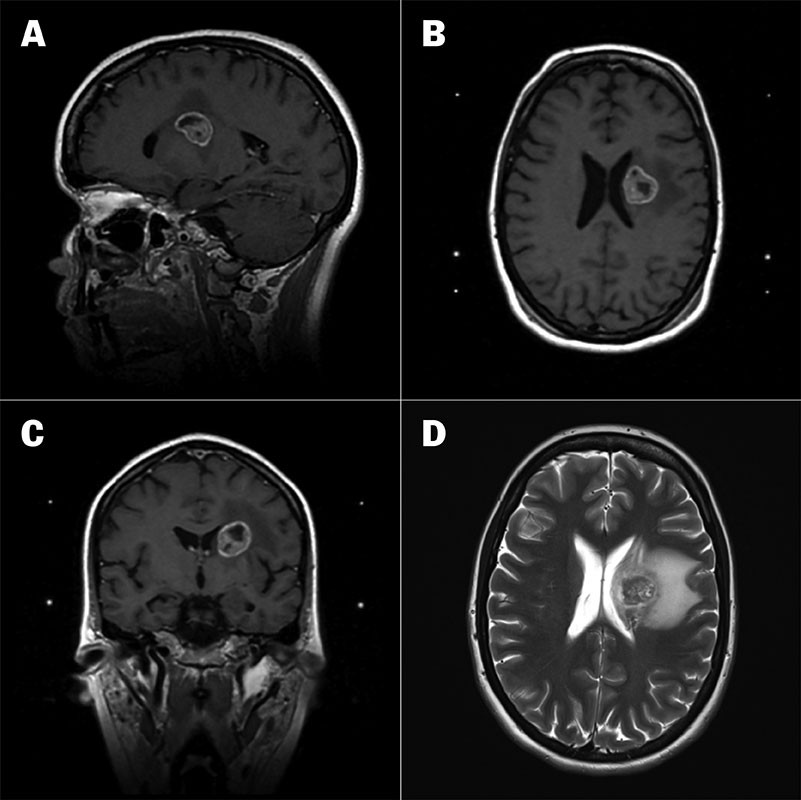

CT- og MR-undersøkelser av hodet avdekket en 23 mm stor ekspansiv prosess med omgivende ødem i venstre talamus som utøvet masseffekt på tilstøtende venstre sideventrikkel (figur 1a–d). CT-undersøkelse av brysthulen avdekket en 5,6 cm stor svulst i høyre lunges overlapp (figur 2). Det forelå forstørrede lymfeknuter paratrakealt på høyre side (stasjon 4R) og paraaortalt (stasjon 6R).